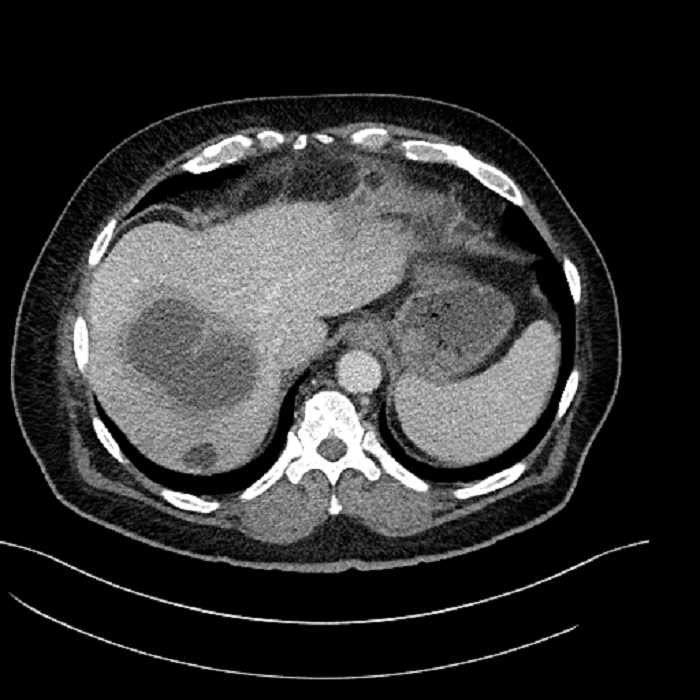

• Large fluid density structure in hepatic segments 7 and 8 measuring 10 x 7 x 7 cm with internal septation and circumferential ill-defined low density compatible with edema

• Peripherally enhancing subcapsular collections along the anterior margin of the left hepatic lobe measuring 3 x 1 cm and 2 x 1 cm

• Clearly marginated fluid density structure in segment 7 and several other scattered tiny hypodensities, which likely represent cysts

Acute sigmoid diverticulitis complicated by a small contained perforation and a large abscess in the right hepatic lobe. Additional small subcapsular abscesses along the anterior margin of the left hepatic lobe.

• The classic CT imaging appearance is a double target sign with internal low density surrounded by an internal enhancing rim (capsule) and a low density external rim (edema)

Hepatic abscess showing the double target sign with low density internally surrounded by a thin inner enhancing rim (red arrow) and ill-defined outer low density rim (yellow arrow). Blue arrow indicates an internal septation. Red arrows: additional smaller subcapsular abscesses. Red arrow: focal contained perforation associated with diverticulitis.